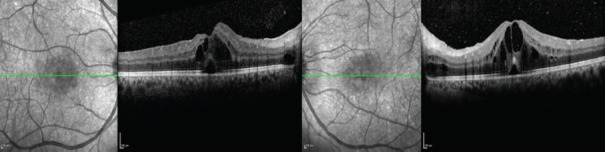

Behçet's uveitis (BU) is a significant form of major organ involvement in Behçet syndrome and is associated with considerable morbidity. Ocular examination is crucial for diagnosing BS and detecting vitreous cells, even in asymptomatic patients. The primary goals in managing BU are to rapidly suppress ocular inflammation and prevent relapses. Initial treatment for posterior segment involvement in BU typically involves immunosuppressive agents combined with glucocorticoids. Biologic agents are increasingly used in BU management, including as first-line treatments for patients with poor prognostic risk factors or sight-threatening uveitis. There is no established consensus on when to discontinue or taper immunosuppressive therapy. Once remission is achieved, the absence of retinal vasculitis should be confirmed with fluorescein angiography, which should be utilized throughout the process of tapering immunosuppressive therapy. In addition to monoclonal tumor necrosis factor-alpha antagonists and tocilizumab, Janus kinase inhibitors may offer the potential for managing BU in the future.

Abstract Image